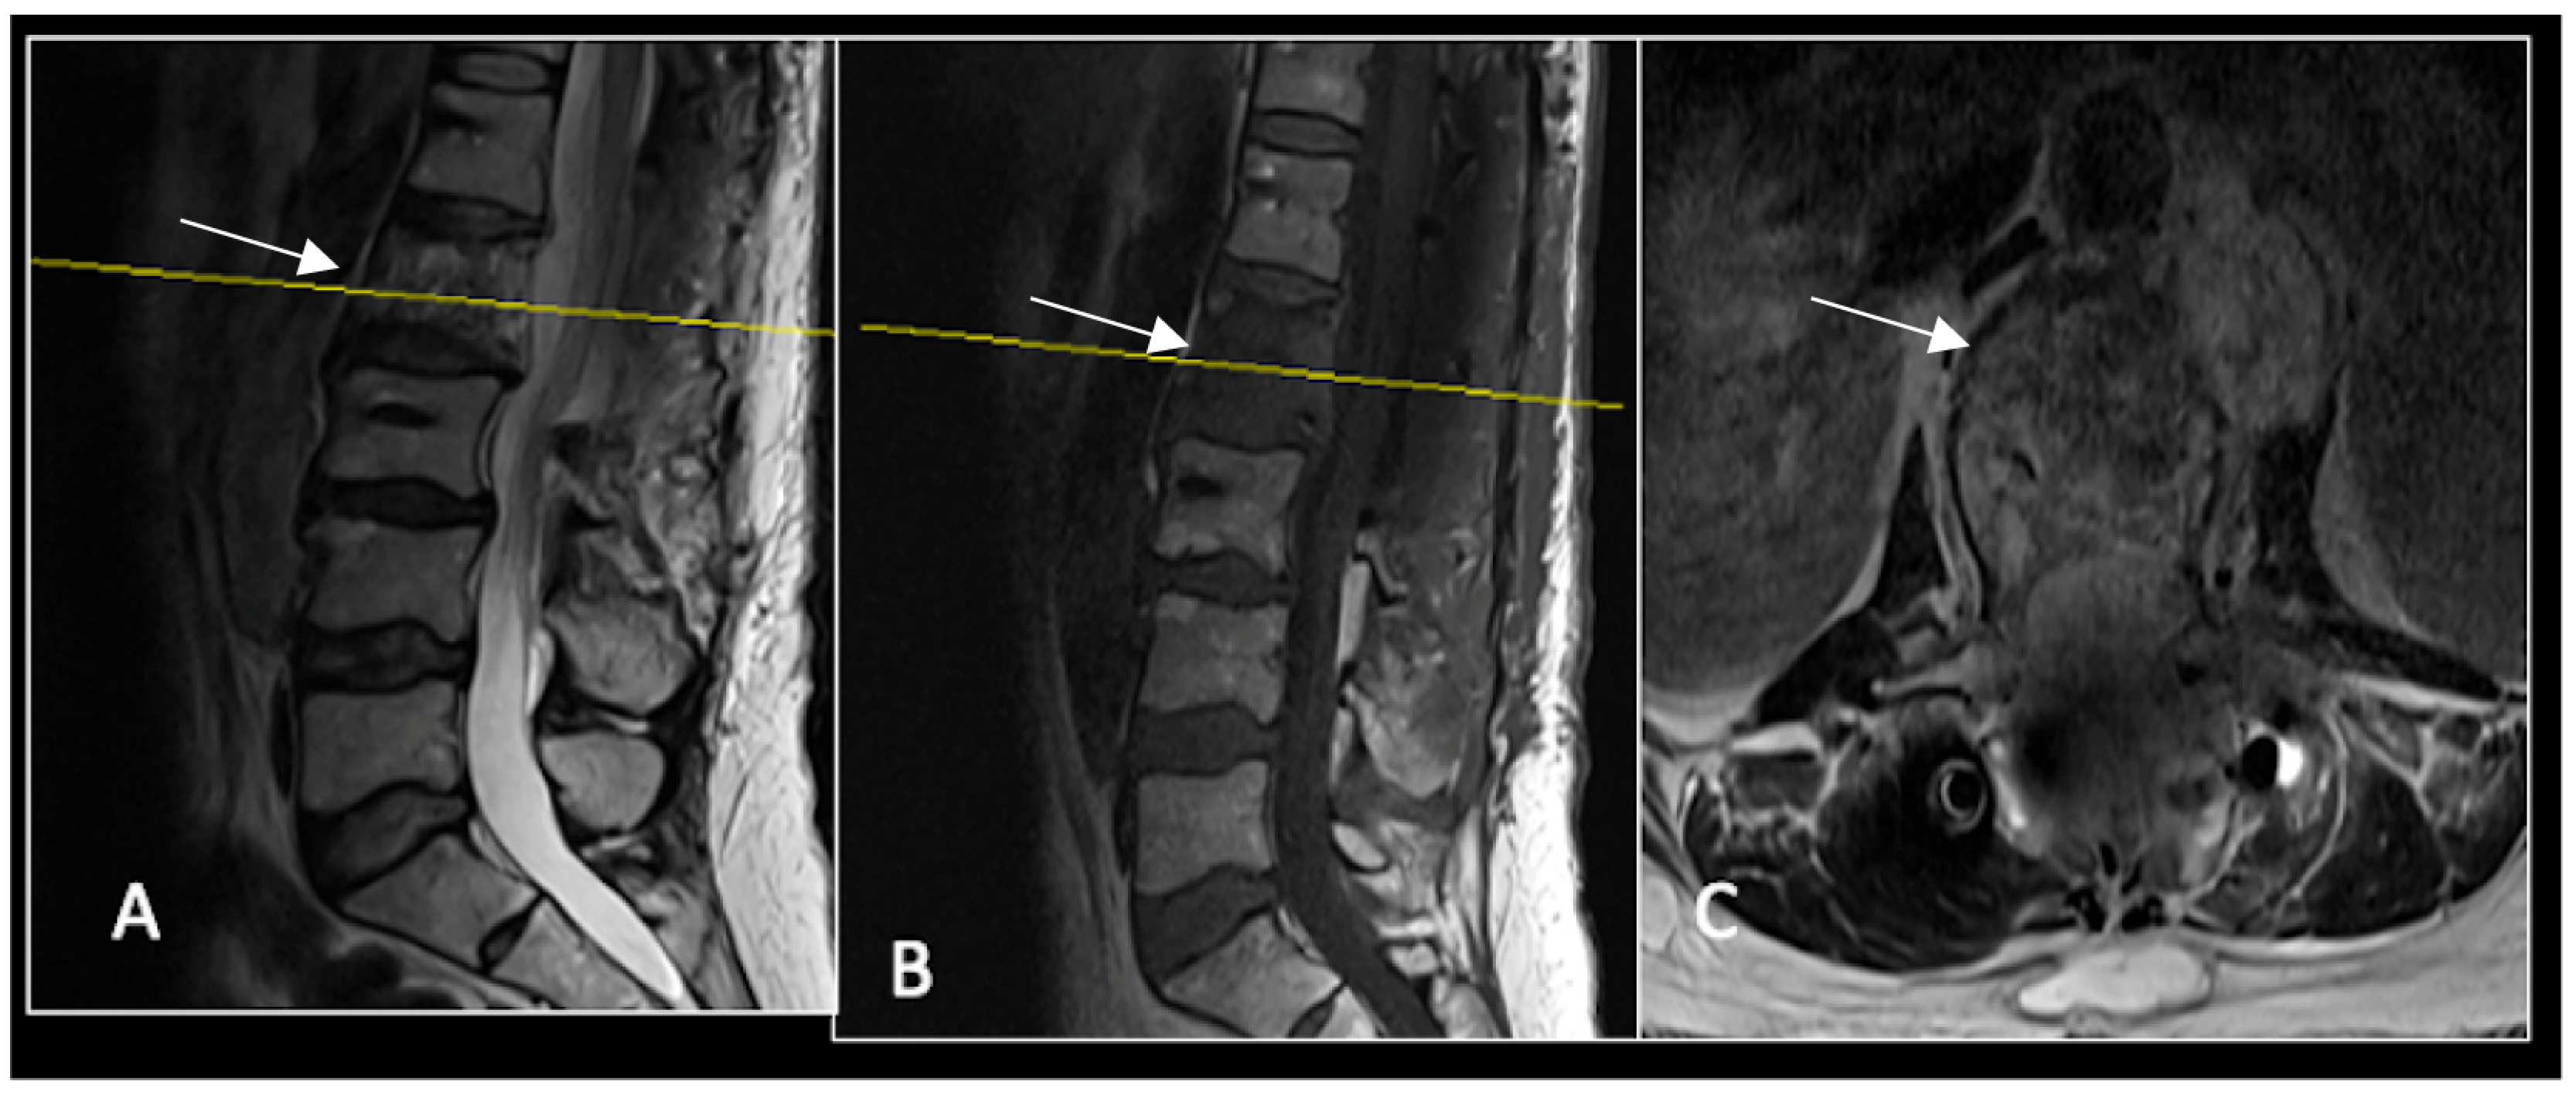

2.4. Case 4: Lumbar Chordoma

This 56-year-old lady was diagnosed with a biopsy-confirmed L2 chordoma (Figure 11). She underwent posterior decompressive separation surgery and instrumental stabilisation T12-L4 using carbon-based implants (Figure 12). Surveillance imaging at 6 months and 12 months post-separation did not show any progression of residual tumour disease (Figure 13 and Figure 14).

Figure 11.

RI demonstrating a lobulated destructive lesion (arrow) with significant epidural extension and compression at L2. The yellow line on the sagittal images denotes the level of the axial image. (A) T2W sagittal; (B) T1W sagittal; (C) T2W axial.

Figure 14.

A 12-month postoperative surveillance MRI shows no evidence of residual tumour (arrow) disease progression. The severity of artefact is reduced. The yellow line on the sagittal images denotes the level of the axial image. (A) T2W sagittal; (B) T1W sagittal; (C) T2W axial.